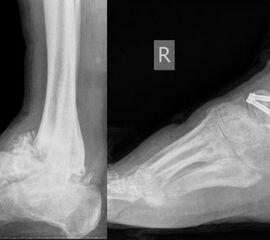

- Operative Behandlung von Druckstellen durch den Zusammenbruch des Fußlängsgewölbes

Als Folge der diabetesbedingten Neuropathie kann es zu dem sogenannten Charcotfuß kommen. Bei dieser Komplikation der Diabeteserkrankung kommt es häufig zu einer Zerstörung der Fußwurzelgelenke und -knochen. Dabei springen die Knochen aus den Gelenken (Luxation) und brechen (Fraktur). Der Fuß verliert an Halt und das Fußgewölbe kann zur Fußsohle durchbrechen (Plattfuß). Hierbei treten Druckstellen durch überstehende Knochenfragmente an der Fußsohle auf, die dann zu Hautschäden führen. Sollten hier konservative Therapiemaßnahmen (Polsterung/Schuhzurichtung) versagen, ist eine operative Korrektur angezeigt. Dabei werden die Knochen mittels Platten und langen Schrauben stabilisiert.

Zum Lesen der Bildbeschreibung und Vollansicht bitte Bild anklicken. Fotos: Alexander Mehlhorn

- Operative Behandlung von Druckstellen durch Fehlstellungen/Instabilität des Rückfußes bzw. Sprunggelenk

Eine weiterer typischer Verlauf eines Charcot Fußes betrifft die Zerstörung der Bänder und des oberen Sprunggelenks. Der Fuß knickt dabei nach innen, manchmal auch nach außen weg. In Schuhen kommt es meist zu Druckstellen im Bereich des Knöchels. Teilweise ist das Sprunggelenk ist so instabil, dass Laufen nicht mehr möglich ist. Oft sind hier die Möglichkeiten einer konservativen Therapie mit Polsterung/Schuhversorgung nicht mehr ausreichend. Kann der Fuß von außen nicht mehr ausreichend stabilisiert werden, ist eine operative Stabilisierung der abgekippten Gelenke mit Platten und Schrauben notwendig um wieder einen belastbaren Fuß zu erreichen.